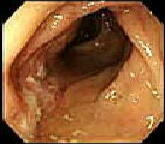

憩室症とは、腸壁にできる小さなポケットで(上図)、多くは無症状ですが、時には炎症を併発し、腹痛、発熱、出血等を来します(憩室炎)。 時には腸壁周囲に膿を作り(膿瘍といいます)、腸閉塞や穿孔等の由々しき事態になることもあります(左中下図)。

憩室症: 小さな穴(ポケット)が数個みられております(上)

憩室炎: 腸壁は赤く、腫れて、管腔は狭くなっております(中)

憩室周囲膿瘍: 憩室から膿が流出しております(下、重症例)